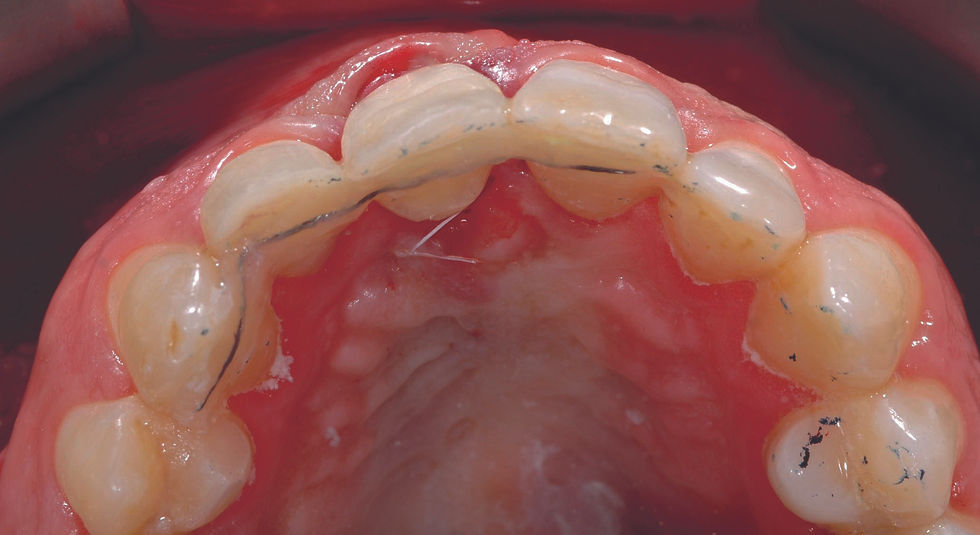

Positioning of the crown of the extracted element, appropriately shaped in its cervical portion and splinted on the palatal side of the adjacent teeth using an orthodontic thread and with adhesive technique.